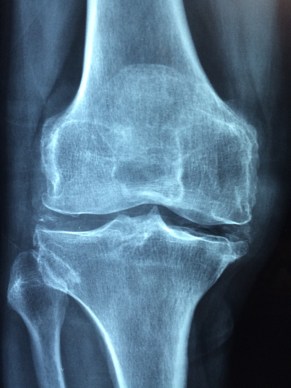

The doctor will then conduct a hands-on examination looking for the source of the pain. This may include palpating the affected area. This helps him or her locate the origin of the pain. However, to determine the underlying cause of the pain, the doctor will often follow the exam with laboratory tests and X-rays.